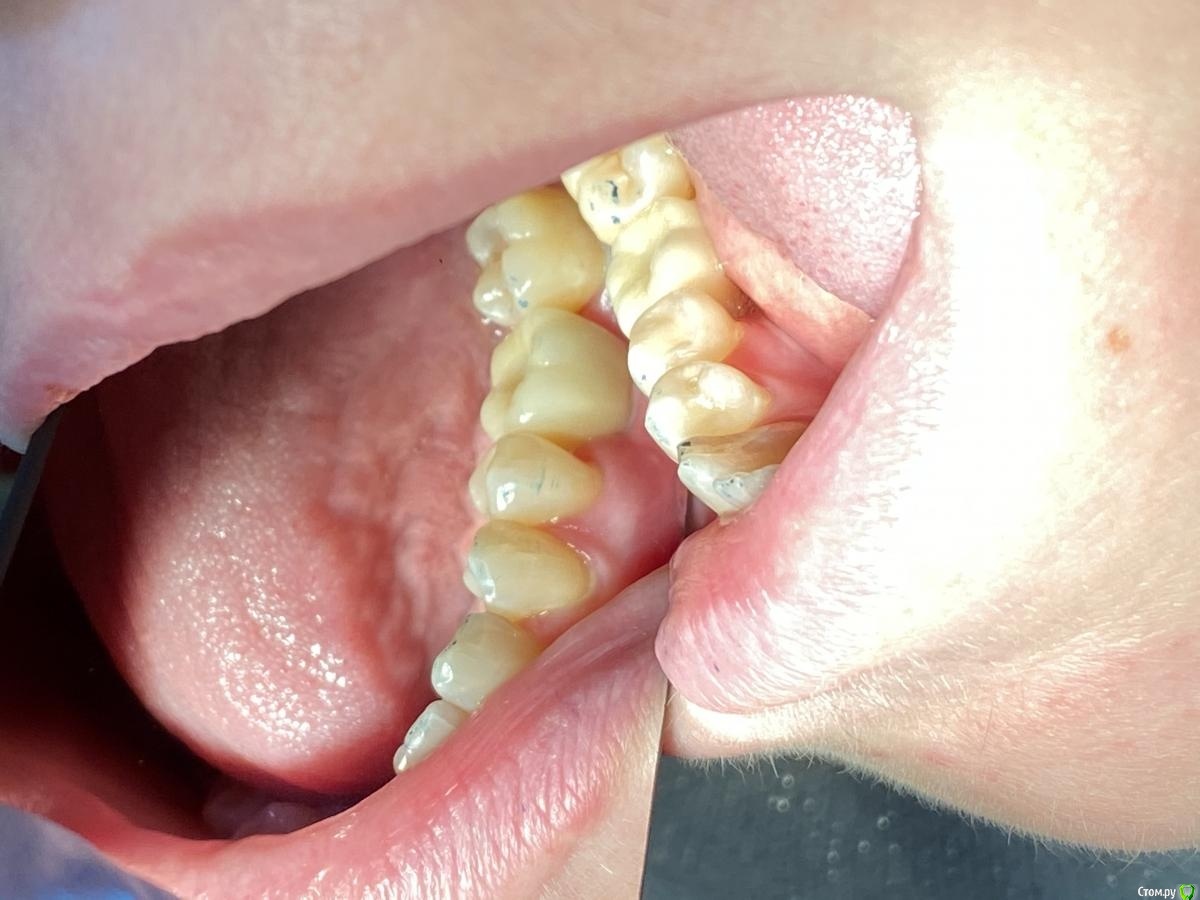

Женька Опубликовано 14 сентября, 2020 Автор Поделиться Опубликовано 14 сентября, 2020 Ну как-то вот так... Ссылка на комментарий

Irouil Опубликовано 14 сентября, 2020 Поделиться Опубликовано 14 сентября, 2020 (изменено) Не идеально, конечно, но я бы отправил уже на протезирование так на Вашем месте, прикрепленка есть, кортикалка по шейку Если включать перфекциониста, то можно пончо сделать, но нужно отслоиться через прикрепление эпителиальное, нужно и увеличение, и тунельный острый инструмент или микро хирургическое лезвие, и навык. Испортить тут можно гораздо больше, чем улучшить Основание абатмента пониже и пошире просто взять и пациента натаскать на гигиену, все ок будет Изменено 14 сентября, 2020 пользователем Irouil 1 Ссылка на комментарий

Женька Опубликовано 14 сентября, 2020 Автор Поделиться Опубликовано 14 сентября, 2020 Не идеально, конечно, но я бы отправил уже на протезирование так на Вашем месте, прикрепленка есть, кортикалка по шейку Если включать перфекциониста, то можно пончо сделать, но нужно отслоиться через прикрепление эпителиальное, нужно и увеличение, и тунельный острый инструмент или микро хирургическое лезвие, и навык. Испортить тут можно гораздо больше, чем улучшить Основание абатмента пониже и пошире просто взять и пациента натаскать на гигиену, все ок будетЯ придерживаюсь этого же мнения...Я скорее испорчу то, что получилось. Эти фото с формирователем 4.5, 3 месяца ходили с 4.0На этапе прикручивания 4.5, пациентка отметила легкое жжение... на фдм метрогил был...вот думаю, то ли это на метрогил такая реакция, то ли я что-то задавил? Планировали на тибейзе geo делать... там варианта пошире насколько я знаю нет. 4.5 и размеры по вертикали cut и длинные З.Ы. Вчера у Ильгама Ирековича на курсе впервые познакомился с галилеями от экзама... всего 2.8, быстро привыкли глаза (учитывая, что они не индивидуально под меня были)... это просто какой-то другой мир. Ссылка на комментарий

Марья Моревна Опубликовано 14 сентября, 2020 Поделиться Опубликовано 14 сентября, 2020 Там на пятерке у пломбы с краевым прилеганием и экватором вопросы, лучше решить это до протезирования. Ссылка на комментарий

Женька Опубликовано 15 сентября, 2020 Автор Поделиться Опубликовано 15 сентября, 2020 Там на пятерке у пломбы с краевым прилеганием и экватором вопросы, лучше решить это до протезирования.Там кариес вторичный завелся уже и пятно на семёрке.Хотели во время интеграции залечить... но не сложилось) конечно решим до протезирования Ссылка на комментарий